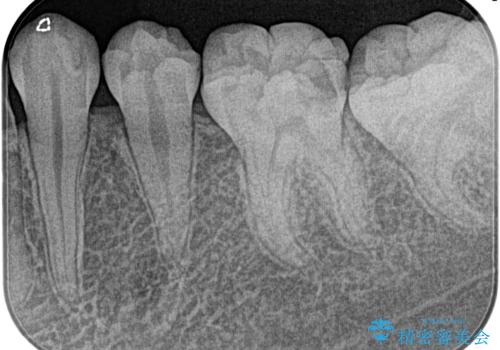

昨晩から激痛。精密根管治療

- 奥歯がズキズキ痛いことを主訴に来院されました。

検査の結果、診断を症候性不可逆性歯髄炎、症候性根尖性歯周炎とし抜髄を行っております。

根管充填はCWCT。

根管形成はマルテンサイト相を有するNi-TIロータリーファイル(NEX MS) 使用。